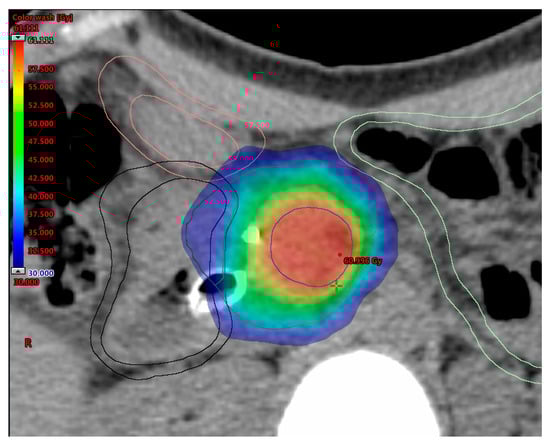

5.4. Simultaneous Integrated Boost (SIB)

| Chuong, 2013 [147] | Retrospective | BRPC/LAPC | 5 | PTV = entire tumor + 3–5 mm | 25 | TVI (region of vessel abutment/encasement) | 35 | OS (m): 16.4/15 PFS (m): 9.7/9.8 BRPC/LAPC | 5.3% |

| Passoni, 2013 [148] | Phase II | LAPC | 15 | PTV = ITV (tumor and enlarged lymph nodes plus motion) + BTV + 5/7 mm | 44.25 | Infiltrating vessel + 1 cm within GTV | 48-58 | DLT: not reached | 0% |

| Mellon, 2015 [78] | Retrospective | BRPC/LAPC | 5 | PTV = GTV (plus motion) + 3–5 mm | 30 | TVI (areas of vessel involvement by tumor) | 40 | OS (m): 19.2/15 LCR: 78% * | 7% |

| Krishnan, 2016 [8] | Retrospective | LAPC | 28 15 | PTV = GTV + 15 mm | 50.4 37.5 | GTV + 2–5 mm | 63–70 67.5 | OS (m): 17.8 PFS (m): 10.2 | No additional compared to SDR |

| Shaib, 2016 [121] | Phase I | LAPC | 3 | PTV = GTV with at-risk area of microscopic spread + 5 mm | 12 | PM = volume between the posterior 1 cm of GTV and mesenteric vessel/retroperitoneal soft tissue | 15 | DLT: not reached | 0% |

| Murphy, 2018 [149] | Phase II | BRPC | 28 | PTV = CTV (GTV + 1 cm margin and elective nodal coverage) + 7 mm | 50.4 | TVI (tumor involvement of critical blood vessels) | 58.8 | R0 resection rate: 97% | 0% |

| Murphy, 2019 [150] | Phase II | LAPC | 28 | PTV = CTV (GTV + 1 cm margin and elective nodal coverage) + 7 mm | 50.4 | TVI (tumor involvement of critical blood vessels) | 58.8 | R0 resection rate: 81% | 0% |